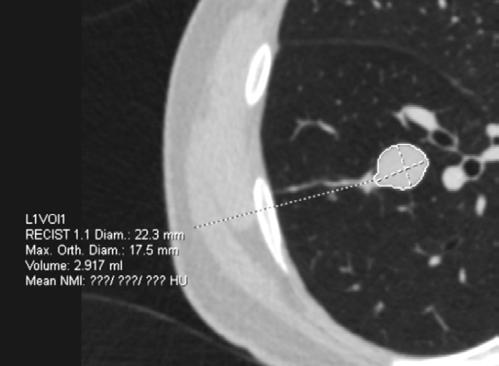

La TC de baja dosis, es la modalidad de imagen más utilizada como método de escrutinio para la detección de lesiones pulmonares, es un estudio rápido, que no requiere preparación previa. ESCANERS DE UN PACIENTE CON

Figura 1-4. Estudio de tomografía simple de tórax, con reconstrucción volumétrica, multiplanares con ventana para pulmón y en mediastino (, en donde se observa el nódulo pulmonar sólido de bordes lobulados hipodensos.

Se le realiza estudio de tomografía simple de tórax en donde se encontró en el segmento anterior del lóbulo inferior derecho nódulo sólido, con diámetro de 22mm, volumen de 2.9ml, condiciona disminución del bronquio segmentario, con secreciones endoluminales distales, de acuerdo a la clasificación de LUNG RADS con categoría 4B, alta sospecha de malignidad. Sin evidencia de lesiones nodulares en el resto del parénquima.

El sistema LUNG RADS para la evaluación de nódulos pulmonares observados en TC de tórax de baja dosis, establece categorías del 0 al 4, dividiendo ésta última en 4A, 4B y 4X, en el caso de los nódulos 4B se establece que son nódulos sólidos con diámetro de 15 mm en el estudio basal o nódulos subsólidos con porción sólida de 8 mm, en la versión actualizada del 2022, se agregan quistes aéreos atípicos con engrosamiento mural o componente nodular mural. La recomendación para esta categoría es la realización de PET CT y/o toma de biopsia.